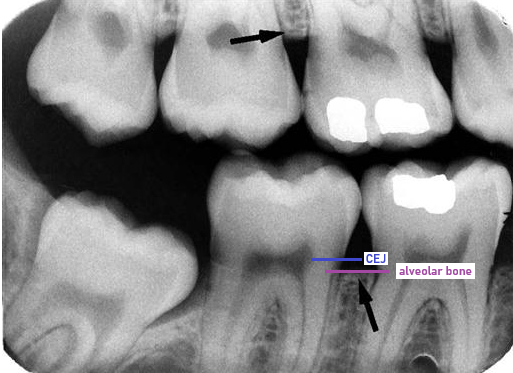

alveolar crest

coronal-most portion of the alveolar process

in health, located 1 to 2 mm apical to CEJ

The height of the Alveolar Crest is in health

1-2mm apical to CEJ

WHY there’s 1-2mm between CEJ and alveolar bone; 1-2mm represents supra-crestal tissue attachment (STA) or biologic width, and supra-crestal attached tissue (SAT)